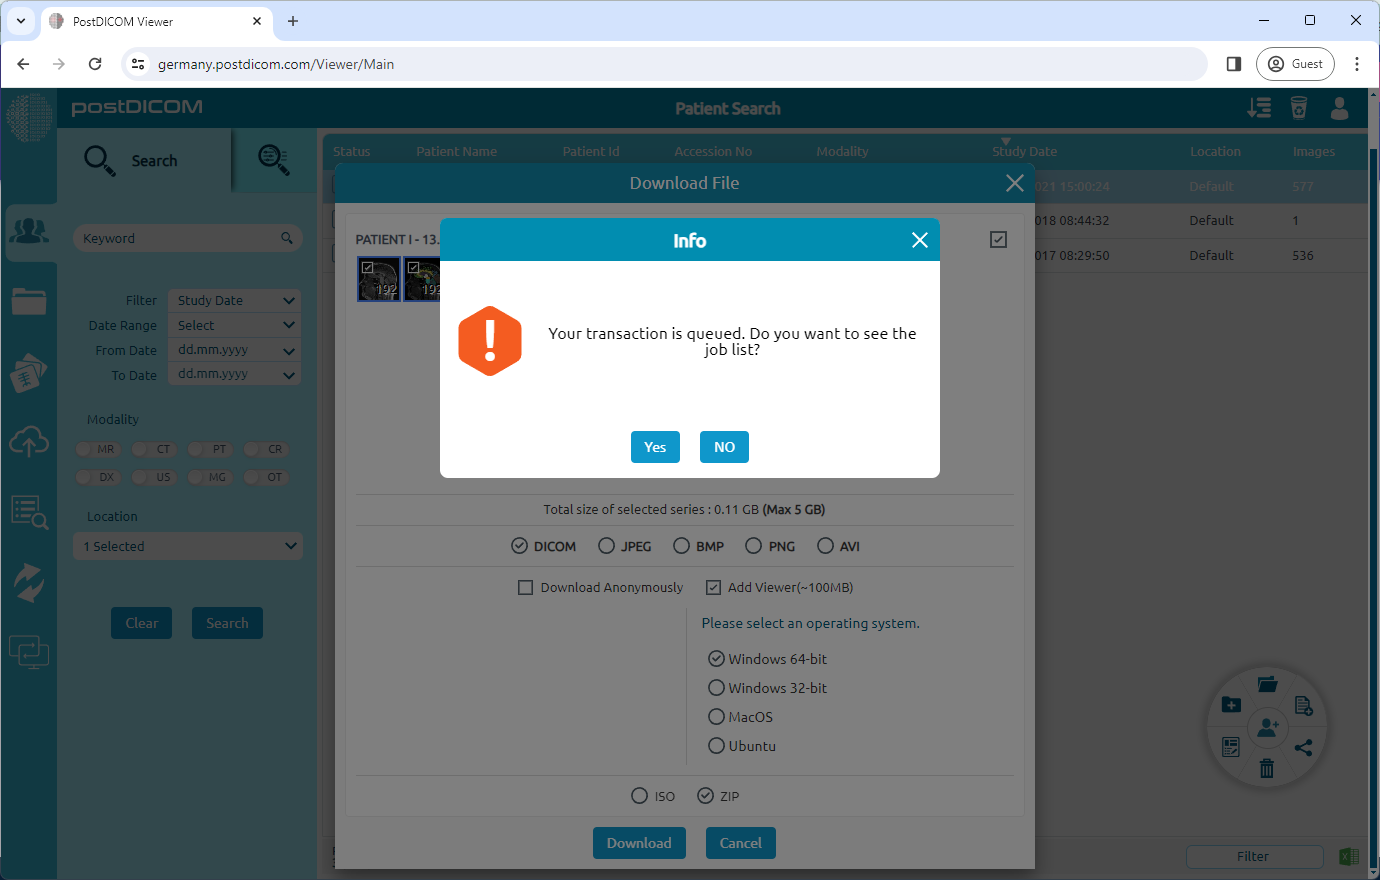

'The download' has been added to the job list as a server job. By clicking the 'Yes' button, you can access the job list and view your progress.